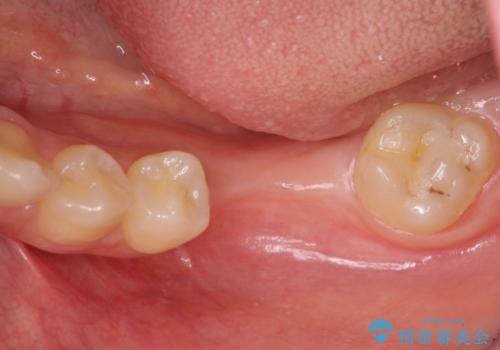

- 虫歯を放置し他院で抜歯後、入れ歯を提案されインプラント治療を希望され来院されました。

CT画像より骨の量は少なくそのままではインプラントの埋入が難しい状態です。

骨造成を行い安定したインプラントの環境を整える治療を計画します。